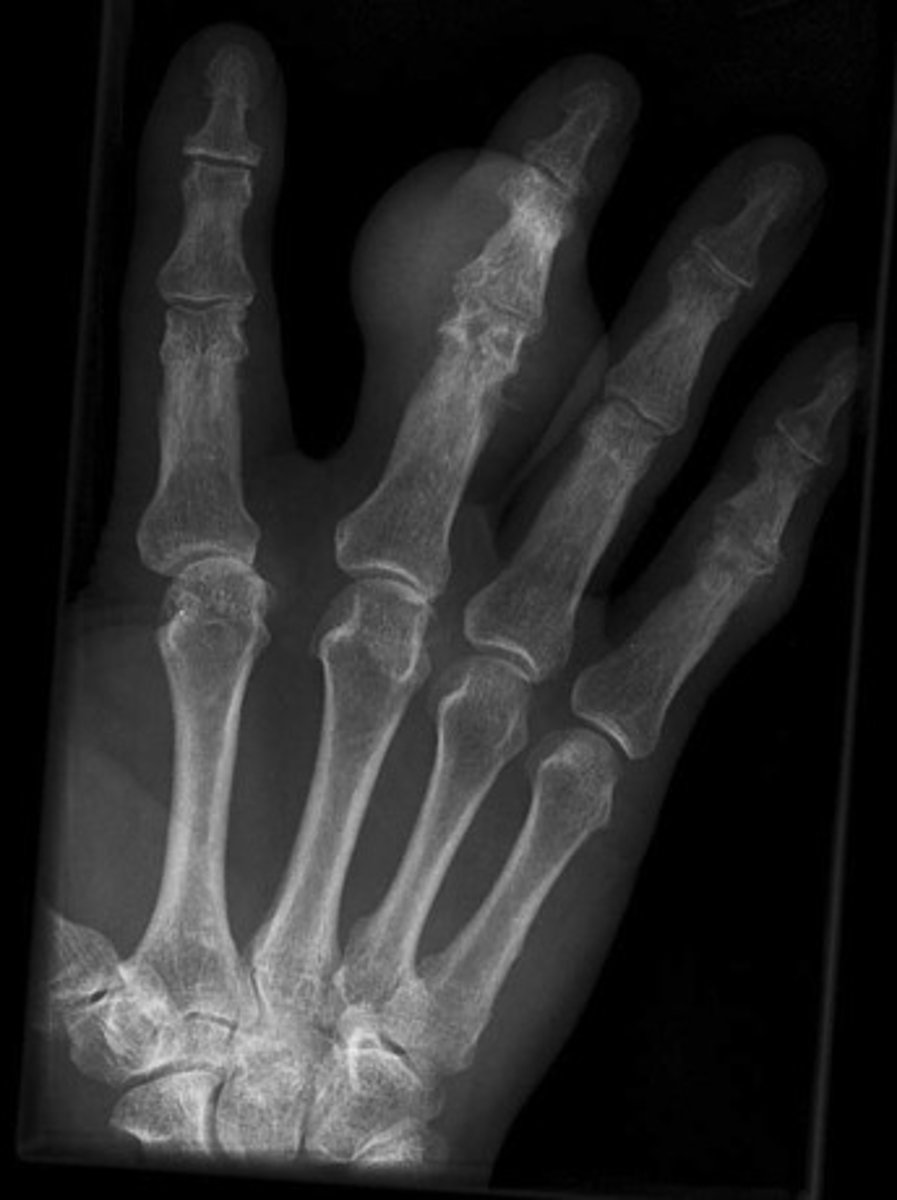

- Erosion of DIP of right digit 2 starting to wrap around

- Dense soft tissue swelling of right digit 2

- Erosion DIP of left digit 2

- Erosion of left ulnar styloid process

- Periarticular osteopenia

What are the abnormal findings on the hand films?

Gout

Diagnosis?